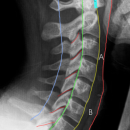

Kriterien für Instabilität (Konsequenz: Operation) an unterer BWS und LWS anhand 3-Säulen Modells von Denis

- Vordere Säule (A): vorderes Längsband, vordere 2/3 des Wirbelkörpers und Diskus

- Mittlere Säule (B): Hinteres Längsband, hinteres 1/3 des Wirbelkörpers und Diskus

- Hintere Säule (C): Wirbelbogen, Ligg. interspinosa et flave, Kapseln der Intervertebralgelenke

3-SäulenModell von Denis

Gemäß dieses Models gelten Verletzungen einer Säule als stabil, Verletzungen von zwei oder drei Säulen als instabil. Bei der Beteiligung der mittleren Säule muss immer von Instabilität ausgegangen werden.